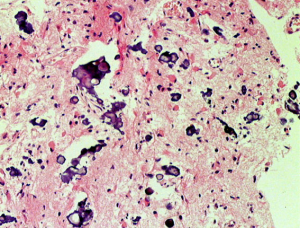

病理像です。左側の部分はperinuclear hallowが多い典型的な乏突起膠腫です。右側の部分ではびまん性星細胞腫の像ですが,その中に乏突起膠腫に特徴的なchicken wireと呼ばれる細い血管網も見られます。乏突起星細胞腫と呼ばれるのですが、腫瘍性格は乏突起膠腫と同じもので,星細胞系腫瘍には入りません。1p/19q欠失があるもののIDH変異がないのでoligoastrocytoma, NOSです。